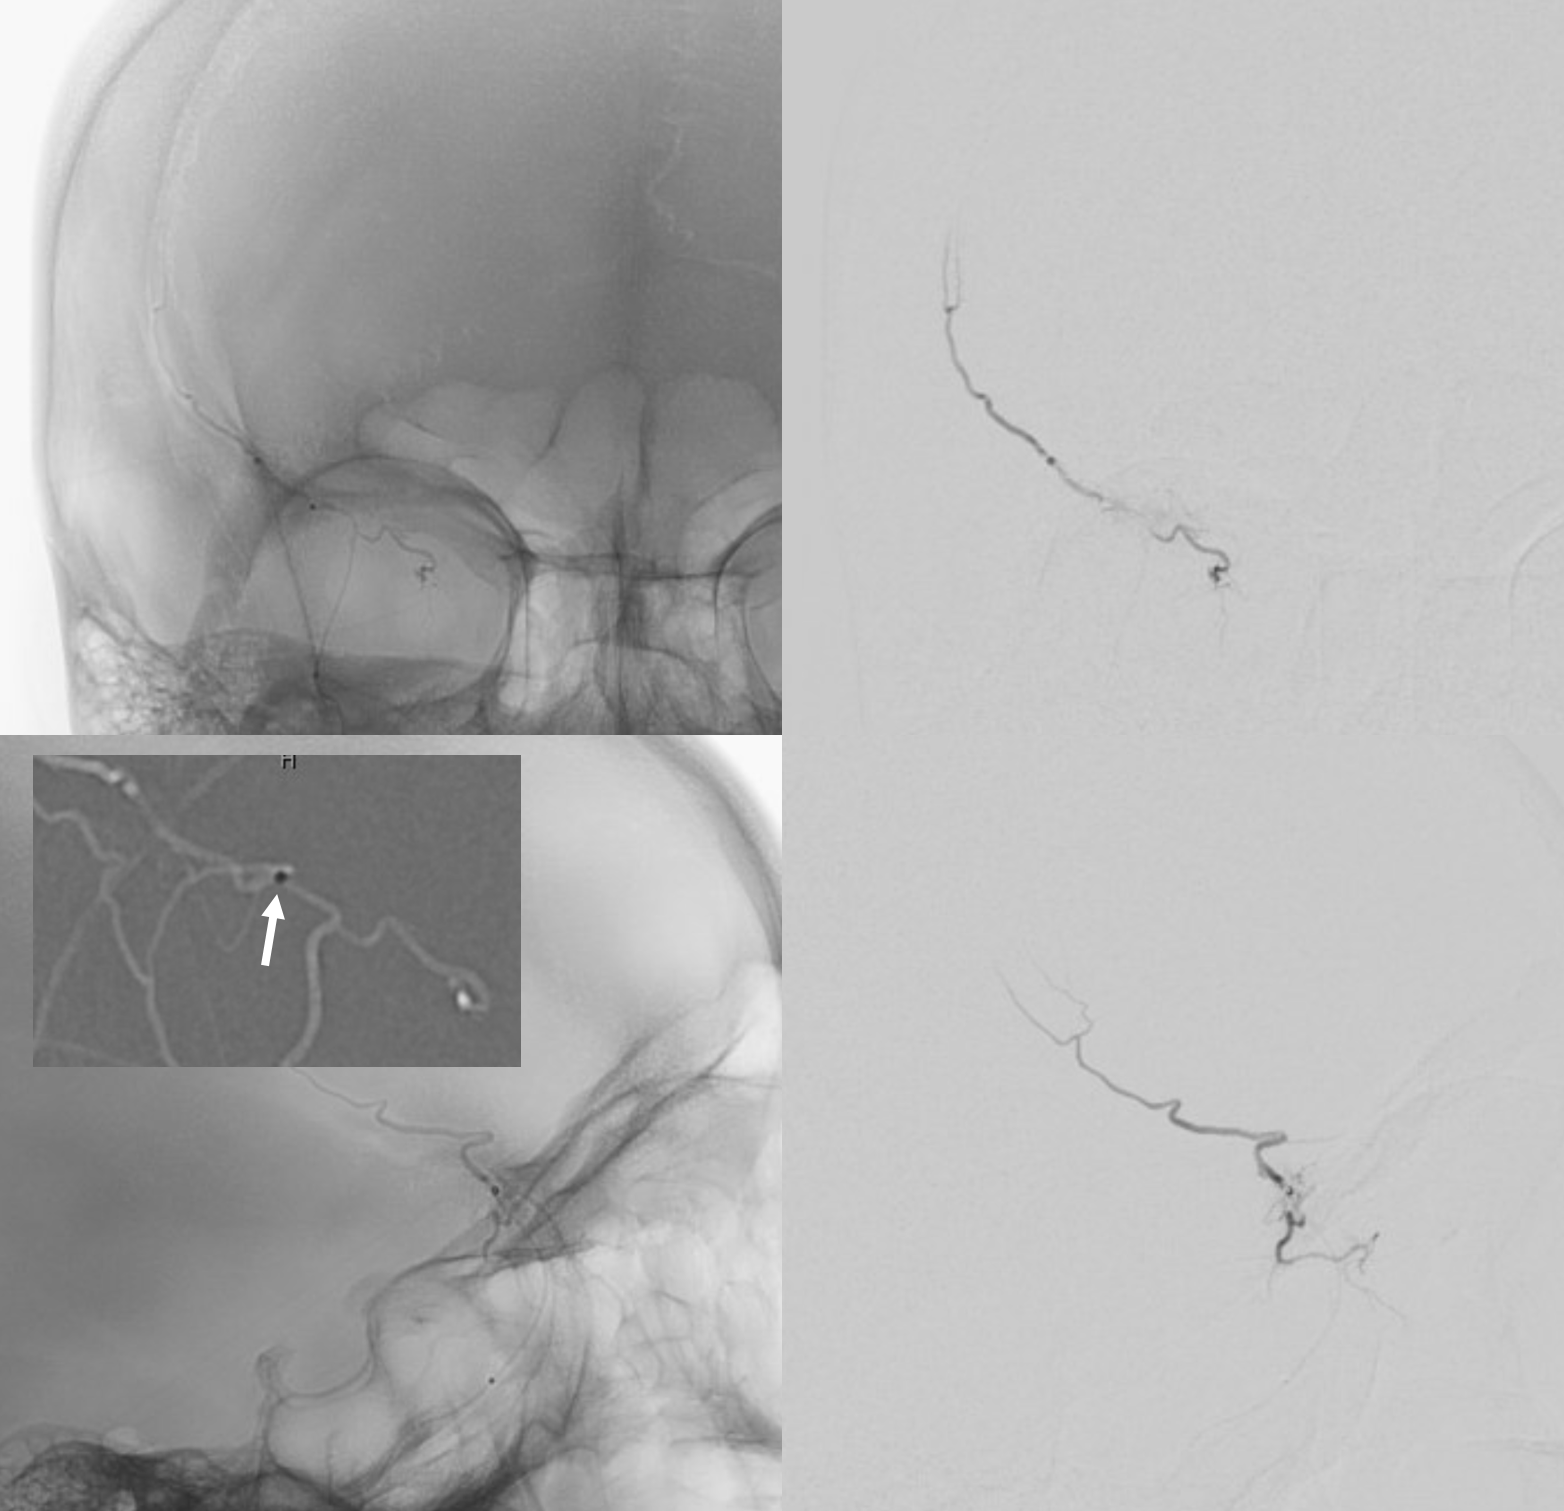

From neuroangio.org

Subdural Embolization Multiple Orbital Anastomoses nBCA Technique Wedge Position Pulmonaliskatheter After further insertion the pac will finally reach its wedge position. the major hemodynamic indices measured on pulmonary artery catheter (pac) are pulmonary artery and. the tip of the catheter lays into the main pulmonary artery, where the balloon can be inflated and deflated for. 2.3.4 wedge position. this video explains about the pulmonary artery catheter.. Wedge Position Pulmonaliskatheter.

Subdural Embolization Multiple Orbital Anastomoses nBCA Technique Wedge Position Pulmonaliskatheter when the balloon is inflated it measures pulmonary capillary wedge. this video explains about the pulmonary artery catheter. 2.3.4 wedge position. the major hemodynamic indices measured on pulmonary artery catheter (pac) are pulmonary artery and. After further insertion the pac will finally reach its wedge position. the tip of the catheter lays into the main. Wedge Position Pulmonaliskatheter.

Subdural Embolization Multiple Orbital Anastomoses nBCA Technique Wedge Position Pulmonaliskatheter when the balloon is inflated it measures pulmonary capillary wedge. the tip of the catheter lays into the main pulmonary artery, where the balloon can be inflated and deflated for. the major hemodynamic indices measured on pulmonary artery catheter (pac) are pulmonary artery and. 2.3.4 wedge position. After further insertion the pac will finally reach its. Wedge Position Pulmonaliskatheter.